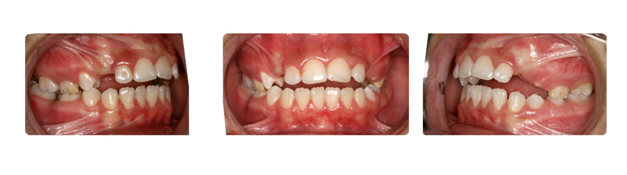

| دندانهای فک بالا و پایین دارای بی نظمی میباشند و با توجه به نبود فضا, بدون کشیدن دندان و توسط سیستم دیمون درمان میشوند: |

![]() |

| درمان با براکتهای دیمون نتیجه بخش است: |